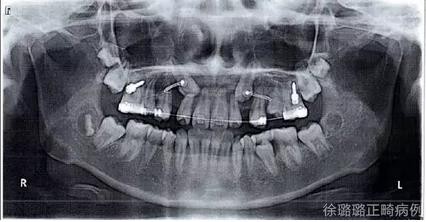

3. .019 × .025" 方不銹鋼絲尖牙導(dǎo)萌,并通過種植體支抗釘牽引尖牙牙冠向遠(yuǎn)中移動(dòng),然后垂直向牽引尖牙向牙合方。

360截圖20170120124750762.jpg

導(dǎo)萌術(shù)中口內(nèi)像

CT 片結(jié)果顯示,上頜雙側(cè)側(cè)切牙與尖牙位置較近,因此早期沒有粘結(jié)雙側(cè)側(cè)切牙托槽,以防止正畸加力對(duì)牙齒造成根尖吸收。